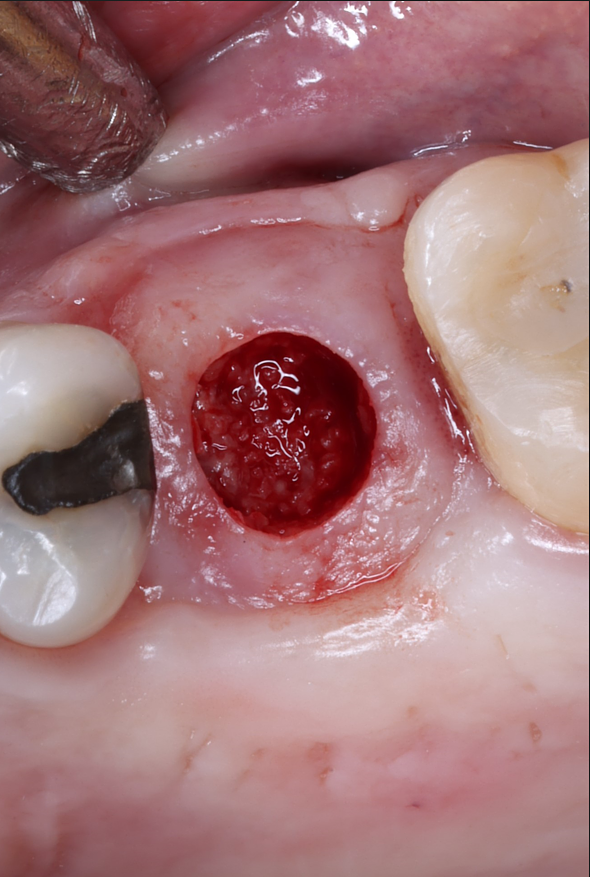

Today, we placed the implant, scanned for the final restoration, just like teaches us to do, and I placed a Neodent healing abutment.

Couple things about this case, I chose to do a tissue punch because the width of the ridge and the amount of attached tissue present. When we use the PTFE membrane for socket preservation, we ultimately grow nice, thick attached tissue, and this is a perfect example of that. I probably only do one or two tissue punches a year.

Notice in the final pictures, the amount of attached tissue is greater around the implant that it is around the natural teeth. Bone is obviously important for implants, but attached tissue will determine how long they last and how healthy they stay.